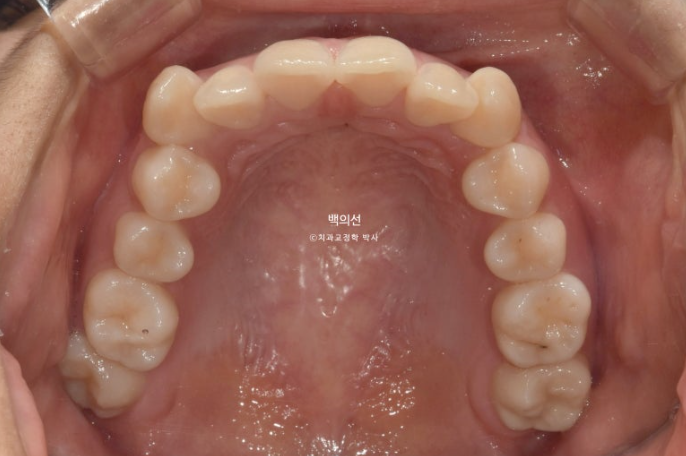

중심선은 잘 맞습니다.

어금니 교합 관계는 1급이고 물샐틈 없네요

치아끼리 심하게 겹쳐져 있던 부위에 블랙트라이앵글은 아쉽지만 잇몸이 내려가 있었던 다수의 치아들에서 잇몸이 다시 차오른 것을 볼 수 있습니다.

통상 한 번 내려간 잇몸은 다시 차오르지 않는다고 알려져 있지만

잇몸이 내려간 원인이 만약 치아가 자리가 없어 밀려나 있었기 때문이라면, 발치교정을 통해 밀려난 위치에서 안정적인 위치로 움직이는 과정에서 잇몸이 다시 차오를 수 있습니다.

물론 20대 초반의 젊은 성인에서 가능한 이야기지만요.